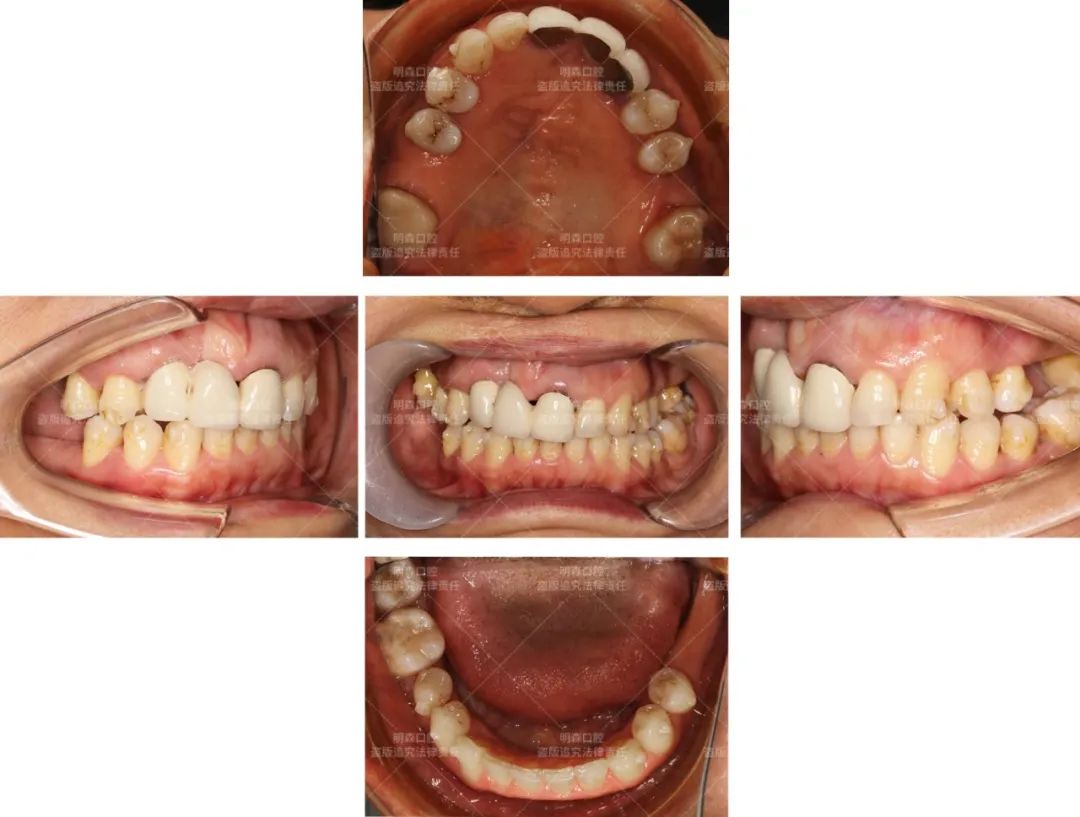

患者控制牙周炎+矫正后的口内照:

现在倪女士牙缝收紧,牙齿也相应变得更整齐,16、26号牙位的空间已经充足。